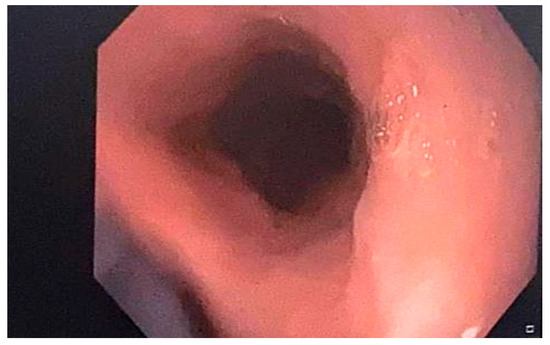

She underwent an upper GI endoscopy which revealed pinkish longitudinal mucosal strips adhering to the middle and lower esophagus, with mucosal erosions observed following detachment, and normal looking mucosa between the lesions. The endoscopic appearance of the esophageal casts, also known as gift-wrap ribbons or wrap paper, was suggestive of EDS or sloughing esophagitis (Figure 1). The stomach mucosa appeared to be normal.

Figure 1.

Endoscopic findings showing the esophageal mucosa with longitudinal strips from the sloughing of the mucosa with a “gift-wrap ribbons” or “crepe-paper” appearance.